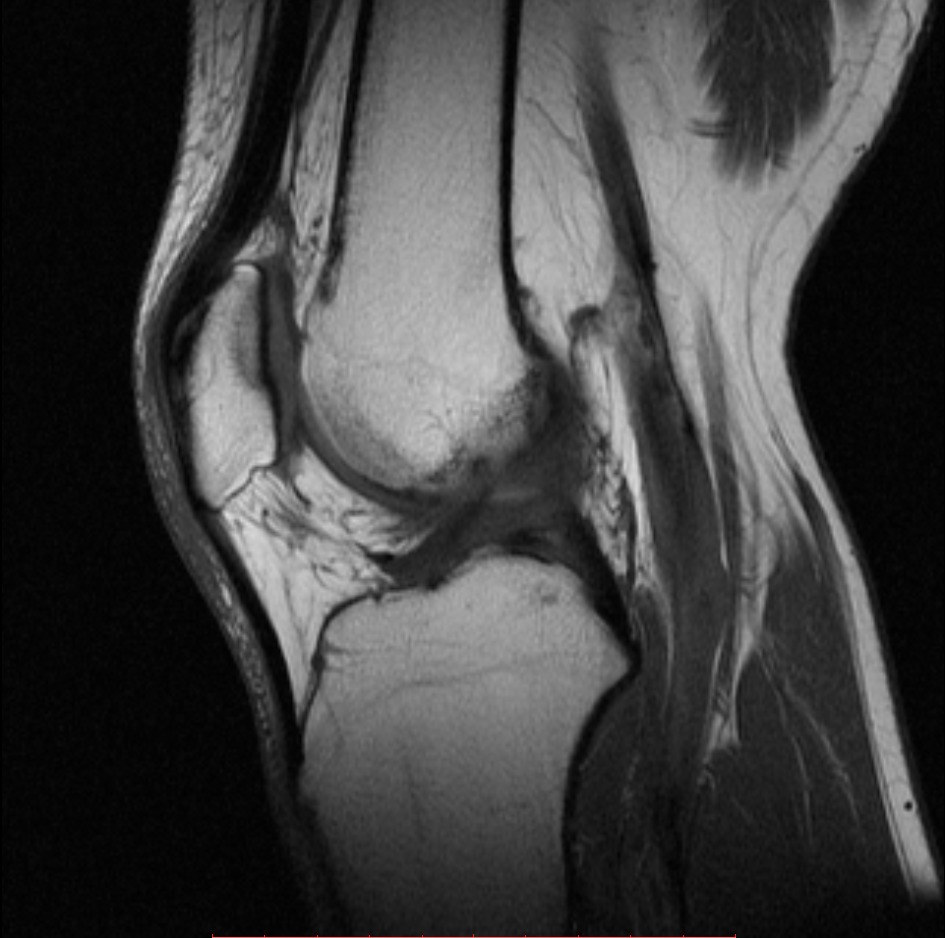

МРТ коленного сустава – это исследование, главной целью которого является выявление и дифференциация патологических изменений в костях, связках, менисках и хрящевой ткани. Благодаря такой процедуре можно выявить даже начальные этапы заболеваний и правильно подобрать подходящее лечение.

МРТ коленного сустава по праву читается одной из самых информативных диагностических процедур. Лучше всего ее выполнять на современном высокопольном оборудовании с мощностью в 1,5 Тесла, которое дает максимально точные данные.

С помощью такого исследования врачи могут оценить состояние хрящевой ткани, костного мозга, связок, менисков и мышечного каркаса сустава.

Более того, МРТ колена дает возможность отследить кровообращение в суставе, выявить объемное патологическое образование и последствия «свежих» и застарелых травм. Именно поэтому процедура часто выполняется как для первичной диагностики, так и для контроля уже выявленных заболеваний.